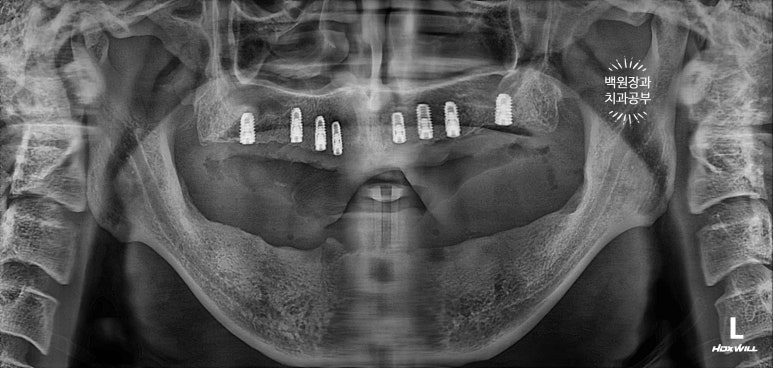

수술 후 촬영한 치과용 파노라마 사진에서 꽤나 예쁘게 심어진 임플란트를 확인할 수 있었습니다.

보시면 상당히 가지런히 임플란트가 잘 위치된 것을 보실 수 있을거에요!

제 포스팅을 많이 보셨던 분들은 잘 아시겠지만, 오른쪽 위 어금니 부위에 상악동 골이식술도 상당히 깔끔하게 잘 된 것을 확인할 수 있습니다.

이렇게 위에는 8개의 임플란트가, 아래에는 6개의 임플란트가 예쁘게 식립된 것을 보실 수 있을겁니다.

엑스레이를 보시면, 티타늄 재질의 오스템 임플란트 정품 !!! 맞춤형 지대주 (custom abutment)가 연결되어 있는 것을 보실 수 있을거에요.

깔끔하게 완성된 보철물은 치과용 파노라마 사진에서 확인하실 수 있고,

비전공자가 보아도 나란히 가지런한 임플란트는 편안함을 줍니다.

똑같아 보일 수 있으시겠지만, 6개월이 지난 후 치과용 파노라마 사진입니다.

보통 임플란트의 초기 실패는 6개월 정도 안에 발견할 수 있기에, 이 시기에 한 번 더 오셔서 체크해보는 것이 중요합니다.